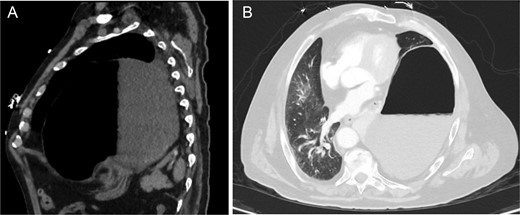

A 69-year-old male with hypertension, hyperlipidemia, diabetes and a prior uncomplicated robotic left nephrectomy for renal cell carcinoma presented to the emergency room for evaluation of chest pain and emesis. He was uncomfortable, tremulous, and tachycardic with absent breath sounds over the left lower field. Initial CT scan showed a Bochdalek hernia containing distended stomach with left lower lobe collapse and transition to normal stomach at the level of the hernia (Fig. 1). Notably, the patient presented one month prior complaining of chest pain and abdominal discomfort that resolved with supportive care. CT scan at the time demonstrated a much smaller defect. At this visit, upper endoscopy showed viable gastric mucosa within the herniated stomach, but the hernia could not be traversed endoscopically.

Pre-operative CT chest w/ contrast showing (A) large left Bochdalek hernia containing a large portion of distended stomach and (B) near-complete collapse of the left lower lobe with mediastinal shift.